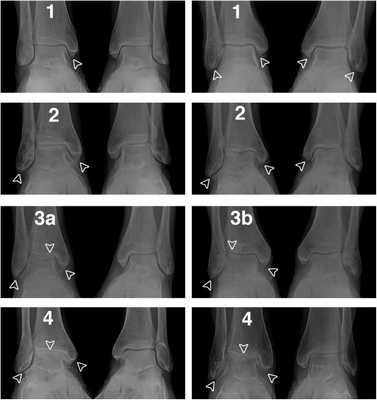

Классификация Н.С. Косинской:

- Начальная стадия. Характеризуется поражением только суставных хрящей. На рентгенограммах может визуализироваться незначительное сужение суставной щели, которое заметно лишь при сравнении с симметричным суставом.

- Стадия выраженных изменений. В дегенеративно-деструктивный процесс вовлекаются кости с развитием субхондрального остеосклероза. При рентгенографии выявляют краевые остеофиты и неравномерное сужение суставной щели как минимум на 50%.

- Стадия ярко выраженных изменений. Проявляется выраженным ограничением подвижности голеностопа. На рентгенограммах видны большие участки остеосклероза, массивные остеофиты, деформация костей и нарушение конгруэнтности суставных поверхностей.

В клинической практике в России и странах СНГ чаще всего используют классификацию Н.С. Косинской.